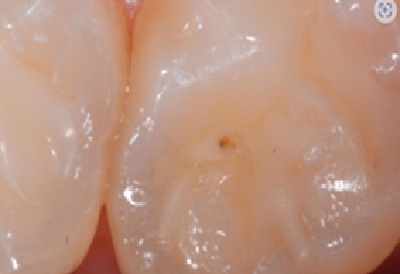

2. Плями і дефекти реставрації

Якщо бульбашка залишається на поверхні композиту, вона утворює заглиблення, де з часом накопичується пігмент.

Це призводить до появи темних плям і естетичних недоліків, що можуть стати причиною невдоволення пацієнта або навіть його переходу до іншого лікаря.